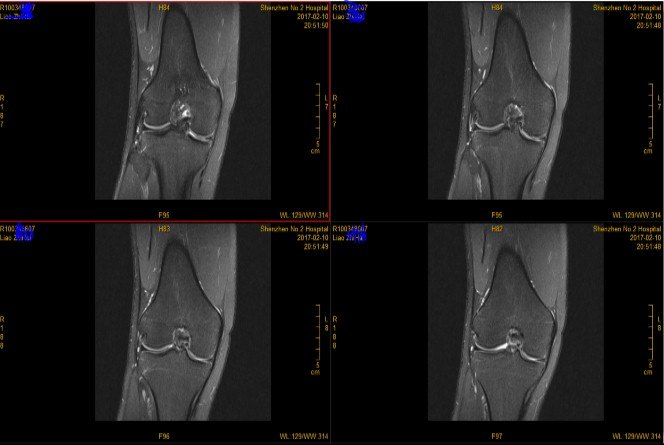

3.MRI(以膝关节为例)

由于MRI和CT一样也 是三维成像,包括矢状面,冠状面和横断面三个层面的扫描。一张MRI片子也是包括医院、姓名、性别、年龄、检查日期、侧别、扫描序列等信息的。不同的示MRI在片子上是信号的高低(CT时密度的高低),也就是说有T1和T2序列(T2序列表现为关节积液是高信号-发白;T1序列表现为关节积液为低信号—发黑或发灰)。因此MRI上不仅有矢状面、横断面和冠状面,还有T1序列和T2序列。

一般来说T2序列更能反应损伤情况,所以平时观察T2序列的图像要更仔细。T1序列主要观察解剖结构,有些医院一般不常规做。

T2序列矢状面:

T2序列冠状面